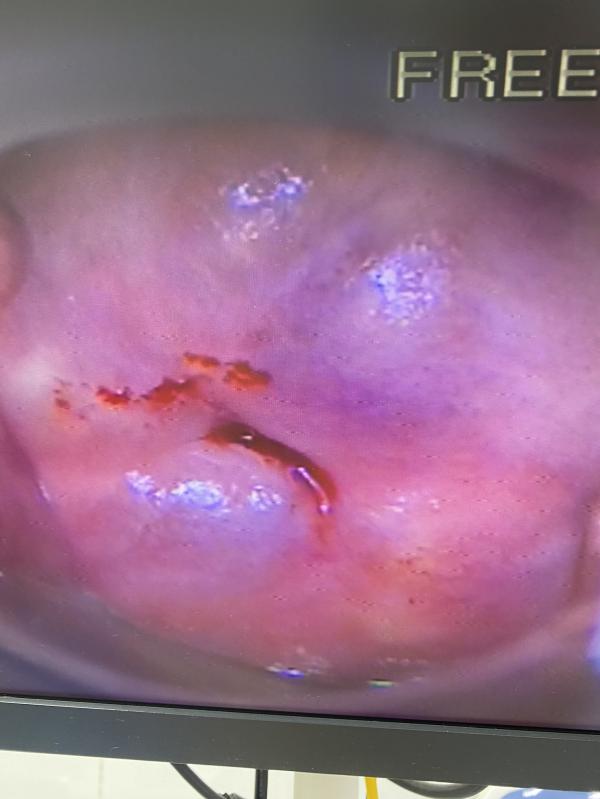

post image 4

Гинекологический приём может быть разный. Зависит от цели, которая ставит пациентка. Всегда продумывайте вопросы к врачу.

На интимную пластику запись предварительная ❤️